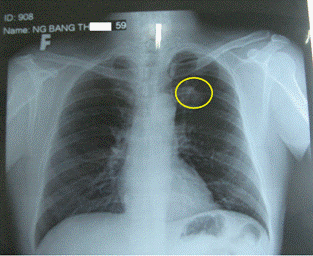

Hình 1: Phim X-quang tim phổi: có đám mờ phổi trái

(trong vòng tròn màu vàng)